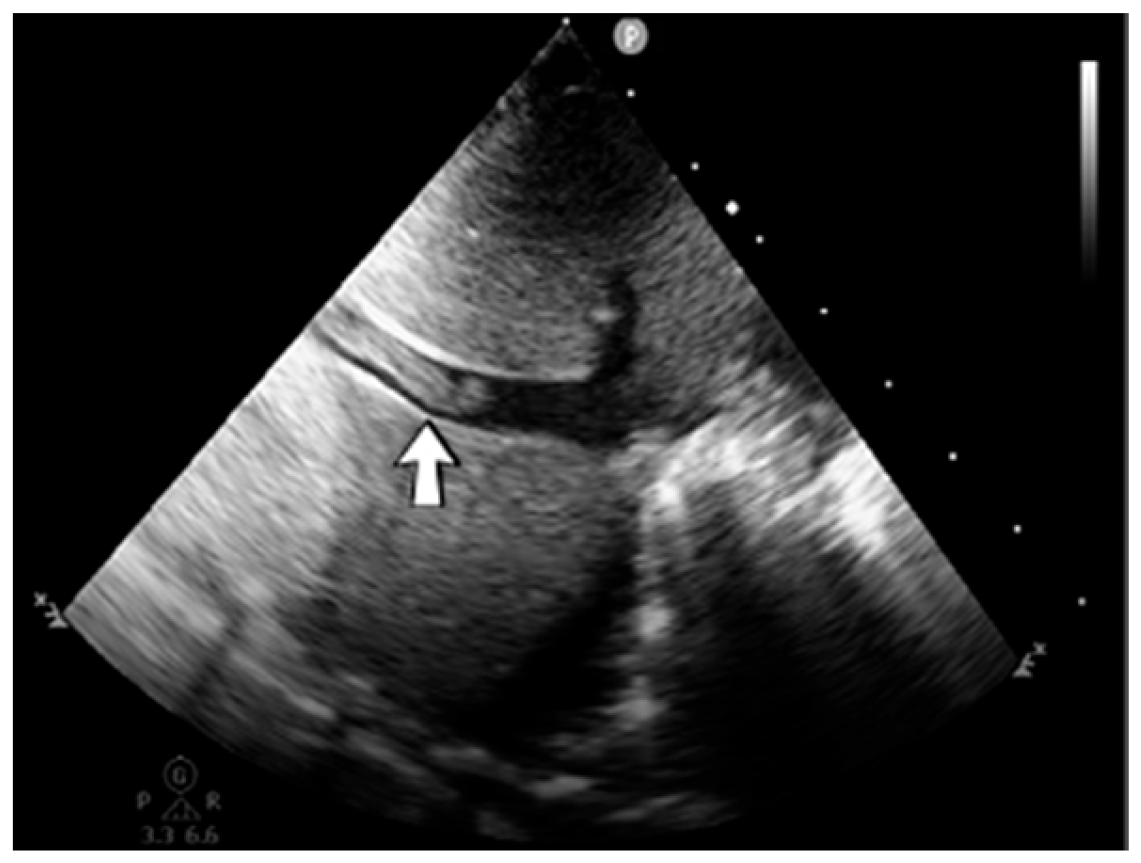

A 19-day-old male neonate (35–36 weeks, 2.20 kg) presented with thrombosis of the right pulmonary artery diagnosed on the same day at another pediatric emergency department, where treatment with continuous heparin infusion was initiated. The admission laboratory findings showed elevated c-reactive protein, modified coagulation tests (ongoing anticoagulation treatment), and elevated D-dimer tests. The cardiac ultrasound identified thrombi in the right atrium and ventricle (Figure 15). Therapy with heparin was continued, to which alteplase was added. After four days of anticoagulation and fibrinolytic therapy, the thrombi could no longer be noticed on ultrasound or CT scan.

Figure 15.

Intracardiac thrombosis was identified on cardiac ultrasound: in the right pulmonary artery (A), the right atrium (B), and the right ventricle (C).

Genetic testing confirmed inherited thrombophilia, with a positive MTHFR C677T homozygous gene mutation and Antithrombin, Protein S, and Protein C deficiencies. A mild elevation of PAI-1 levels was detected. There was limited information about the family history.